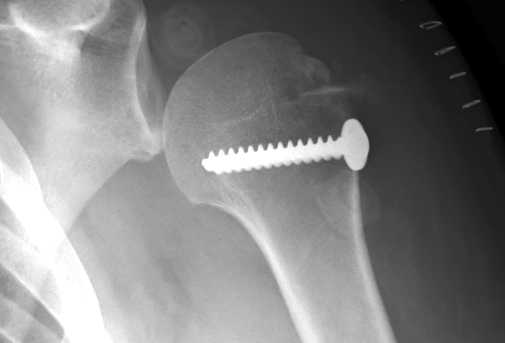

proximal humerus fracture Background ORIF with locking plate Arthroplasty Greater tuberosity fractures Lesser tuberosity fractures / avulsions Book traversal links for Proximal humerus fractures ‹ Pectoralis Major Tears Up Background ›